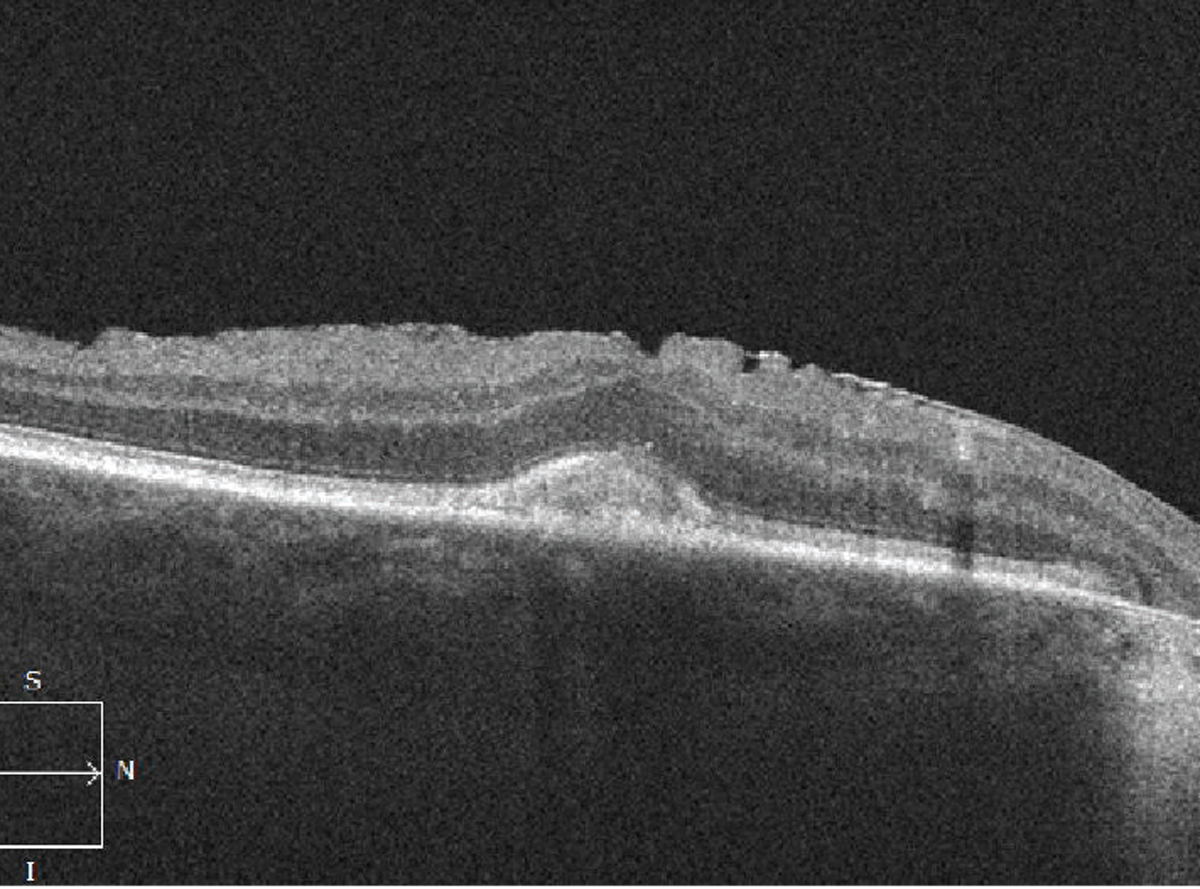

A vascularized PED occurs when abnormal vessels gain entry to the sub-RPE space through breaks in Bruch’s membrane. Signs of a vascularized PED include a notched or shallow irregular border to the PED, which can be associated with fluid, lipid exudate or hemorrhage. A shallow irregular RPE elevation (SIRE) on OCT should raise the suspicion of a vascularized PED or type 1 MNV. In some cases, banding can also be evident on OCT within a fibrovascular PED (Figure 6).

| Figure 6. A) Optical coherence tomography angiography B-scan with flow overlay (left) and en-face scan (right) show a vascularized pigment epithelial detachment. B) Shallow irregular retinal pigment epithelium elevation (SIRE). C) Fibrovascular PED with banding. |